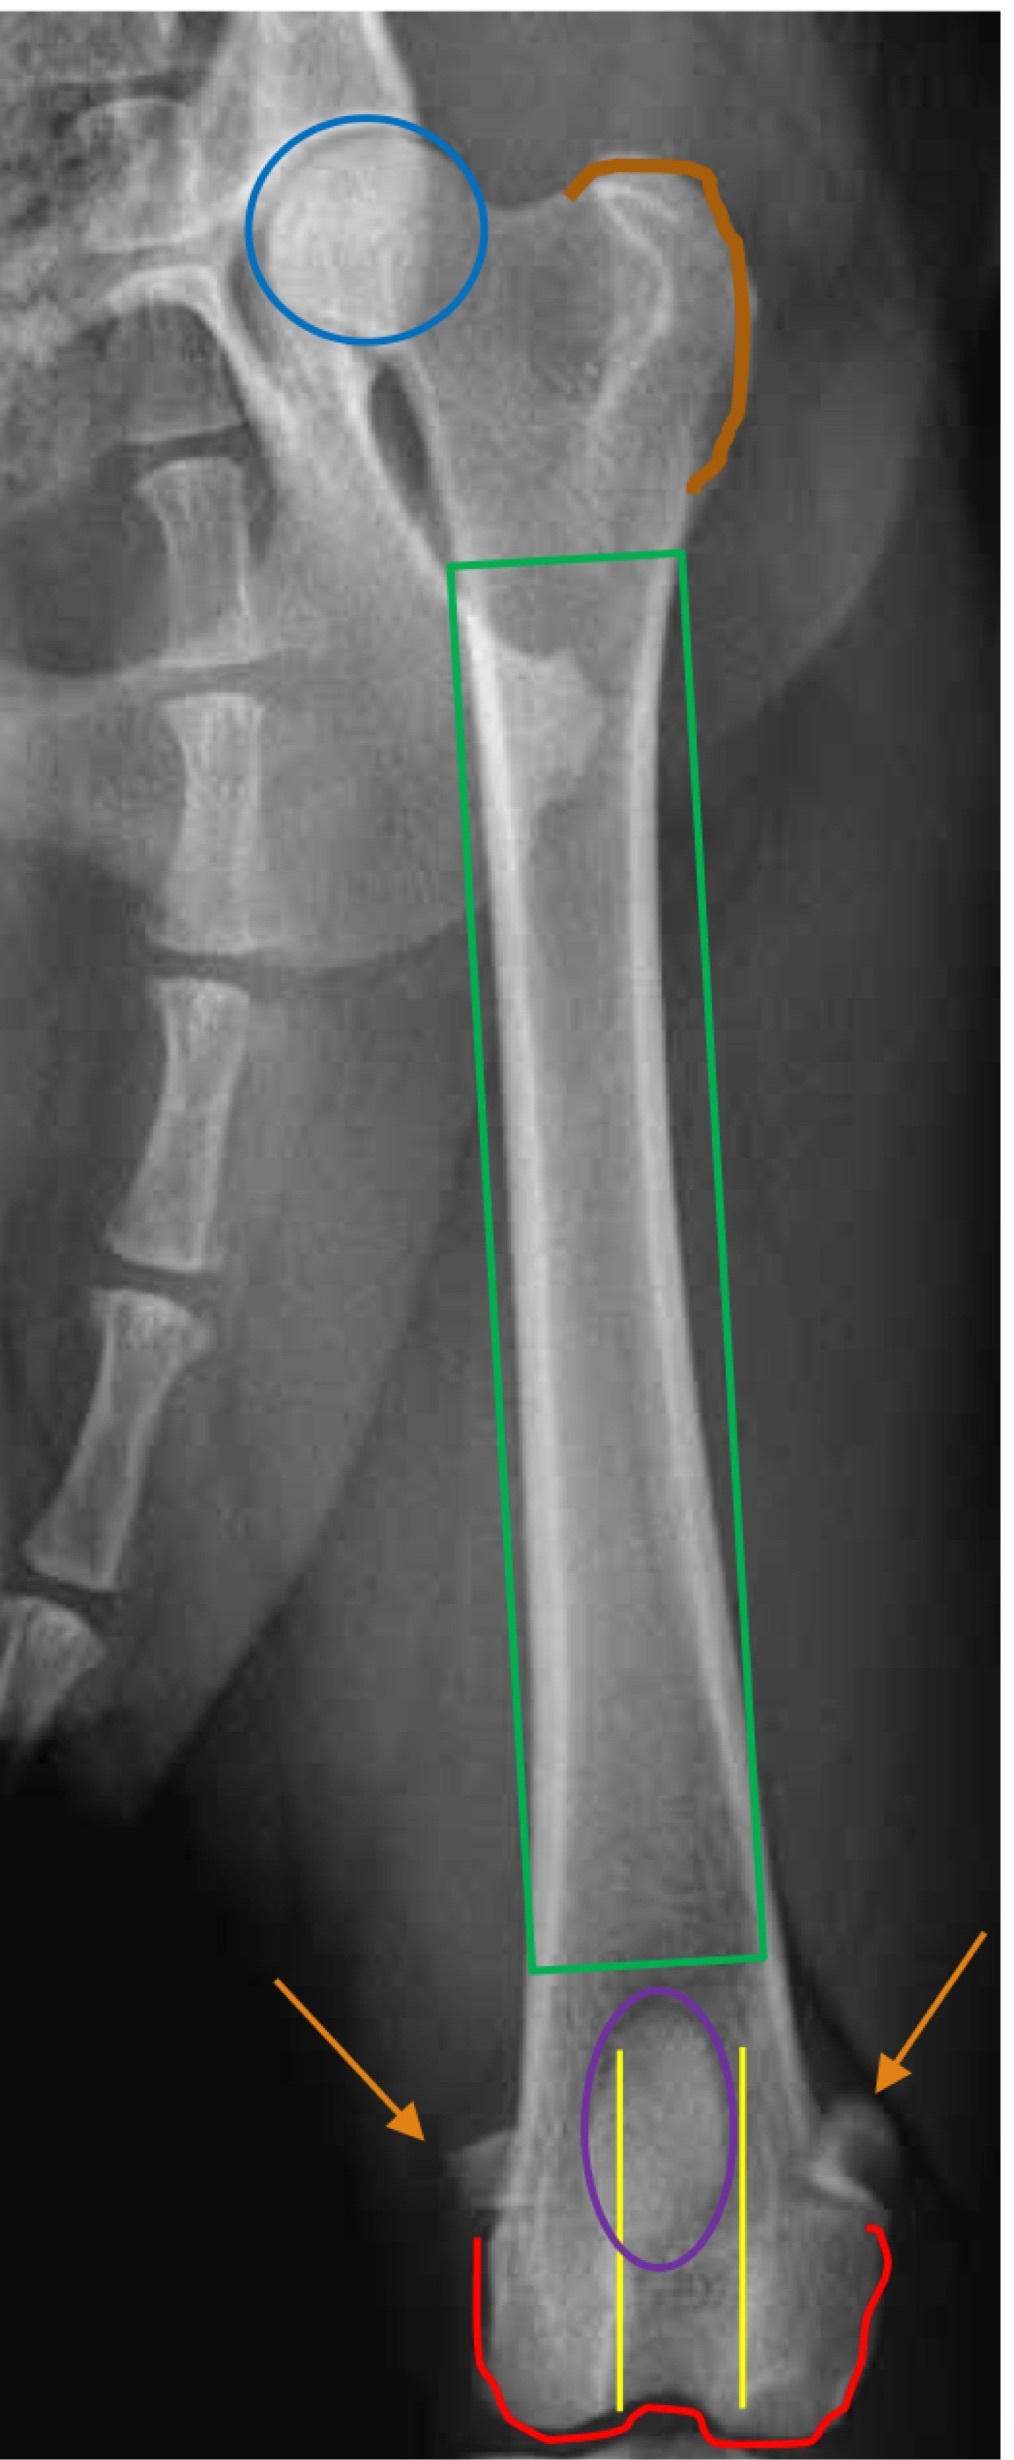

2

Q

Blue ?

Brown line

Green

Yellow

Red

Purple

Brown arrows

A

Blue- femoral head

Brown line- greater trochanter

Green- femoral shaft/ diaphysis

Yellow - femoral trochlea

Red- femoral condyle

Purple- patella

Brown arrows- fabellae